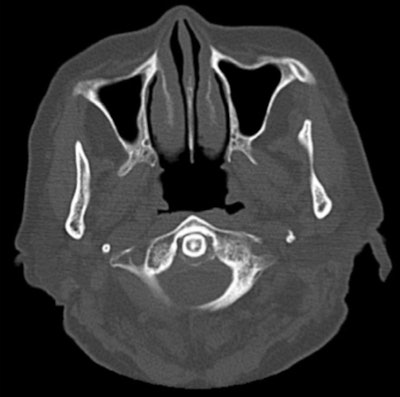

Plain CT scan showing calcification surrounding the odontoid process. An axial CT scan of the cervical spine shows calcification on the posterior aspect of the odontoid process.

Crowned dens syndrome is a subtype of acute calcium pyrophosphate crystal deposition disease (CPPD) and features arthritis in the cervical spine and crownlike calcification around the odontoid process on computed tomography (CT) scanning. Crowned dens is linked with severe systemic stress, including surgical stress, and it initially causes fever and neck pain. In Europe and the U.S., the prevalence of CPPD is between 4% and 7% in adults.